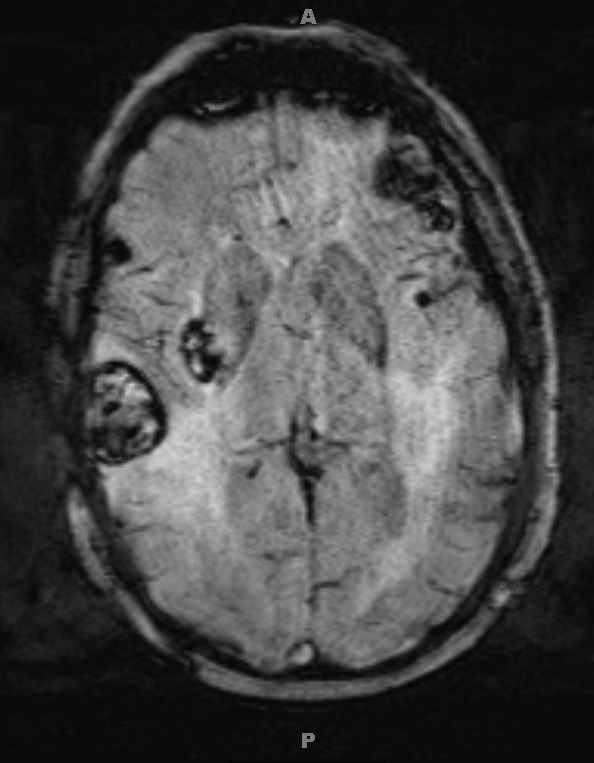

Multiple metastases are seen in SWI (2A2) and T2-weighted contrast applied (2A3) scans.